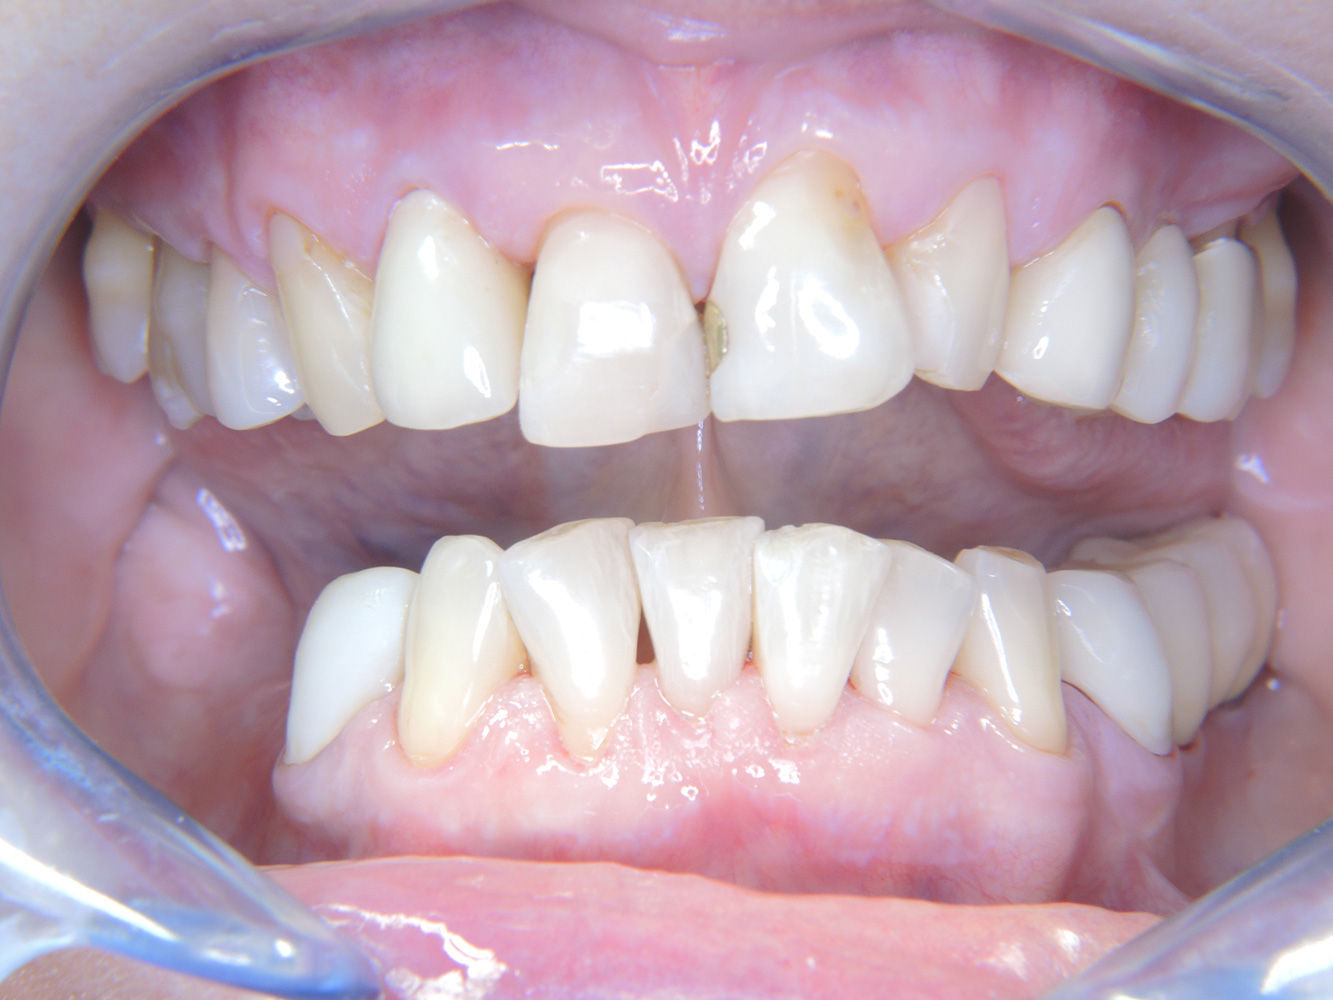

La paciente de 68 años no tiene enfermedades previas relevantes de la salud general ni toma medicación; sus hábitos alimentarios tampoco suponen un riesgo especial. La paciente tiene dos implantes (tercer cuadrante, desde hace cinco años) y una enfermedad previa periodontal (periodontitis en etapa IV, grado B) con pérdida dental. Actualmente las condiciones periodontales son estables, pero la periodontitis aumenta de manera determinante las complicaciones biológicas cuando se realizan implantes y puede ocasionar la pérdida de un implante (21). Para la sesión de profilaxis se hacen cuatro recomendaciones.

Aunque las condiciones sean estables, no debe descuidarse la motivación y la formación de esta paciente. Hay que prestar especial atención a que aprenda a cómo cuidar los implantes correctamente. Aquí en particular, un buen mantenimiento en casa puede jugar un papel importante en la estabilización a largo plazo de la salud oral y del implante.